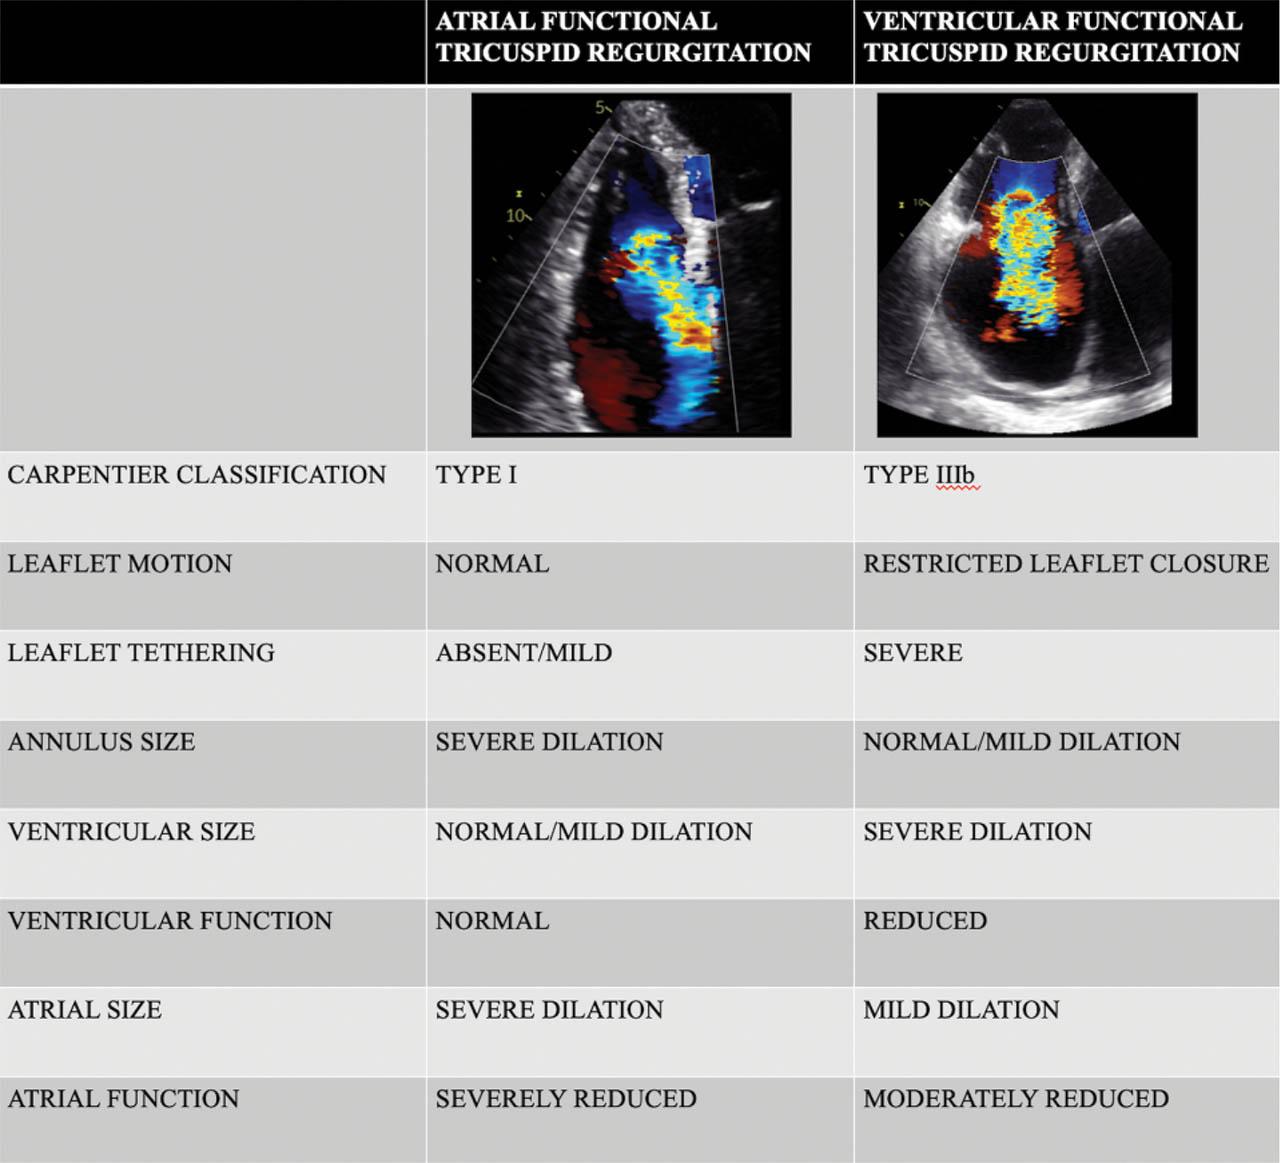

The proposed model of atriogenic regurgitation-typically with long-standing persistent AF - implies a significantly remodeled RA that promotes a marked and progressive dilatation of TV annulus in the presence of no or minimal dilation of the RV4,25. TV annulus is considerably enlarged in AF patients, even with less than severe FTR, and independently of the presence of cardiac structural abnormalities, supporting that TA dilation is the direct consequence of AF itself, rather than the result of FTR26. Compared with ventricular FTR patients and for similar FTR severity, patients with atrial FTR had increased dimensions and posterior displacement of the TV annulus, larger RA, and smaller RV6. Moreover, in patients with so-called “idiopathic FTR” (most of them being actually atrial FTR due to AF), Topilsky27 observed that the RV assumes a triangular shape with dilation occurring at the basal level, resulting in a large TV annular area without leaflet tethering (Figure 1). In contrast, in patients with pulmonary hypertension and ventricular FTR, the RV becomes elliptical due to dilation occurring at the midventricular level, resulting in significant valvular tethering with no or mild TV annular dilatation (Figure 2). Thus, the tethering of TV leaflets is commonly seen in patients with a ventricular form of FTR (with/without significant annular dilation) due to pressure/volume RV overload, while in atrial FTR due to AF the tethering is characteristically absent because the RV is normal. Once the pathophysiological cascade is initiated (either by ventricular or atrial factors), a vicious cycle ensues, with progressive FTR and further dilatation of the TA due to either RA or RV volume overload, resulting in further FTR and ultimately a combination of both atrial and ventricular FTR4,28,29. Therefore, in advanced stages with massive or torrential FTR, marked remodeling of TV apparatus, and secondary RA and RV dysfunction due to longstanding volume overload, it may be more challenging to distinguish the primary cause of FTR6,16. However, the prognosis of massive/torrential FTR is severe30,31 and there is likely little clinical benefit in clarifying the pathophysiological sequence at this advanced stage of the disease. Figure 3 presents the main imaging features that may help in differentiating the atrial FTR from the ventricular FTR.

Figure 1

Comparison between atrial and ventricular functional tricuspid regurgitation; adapted from 5.